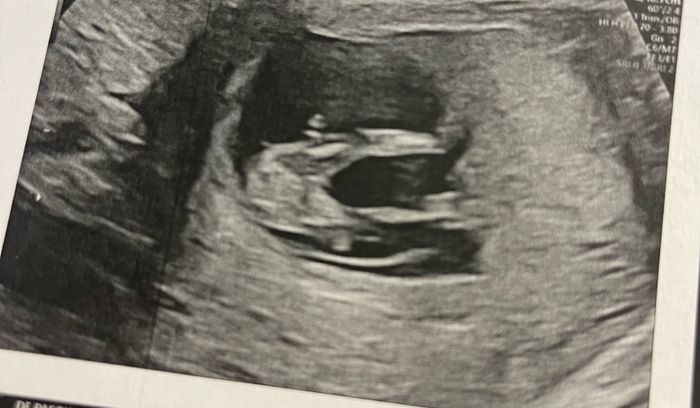

Ciao ragazze, lunedì scorso ho fatto eco genetica a 11+5 ma bebè misurava 12 settimane, ho fatto dna fetale che dovrebbe arrivare questa settimana, ma nel frattempo per ingannare il tempo e l’ansia, c’è qualcuna che se ne intende di nub theory? Io un pochino sì e quindi ho una mia idea. Sia per il tubercolo, sia per la posizione della vescica, rispetto alla spina dorsale… ma magari qualcuna qui ne capisce più di me, maschio o femmina?vi lascio un po’ di foto

cfb_2067805.jpg

cfb_2067807.jpg

cfb_2067809.jpg